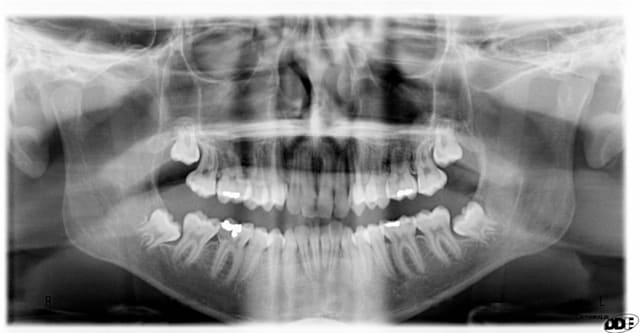

Changement en 4 ans de 17ans à 21 ans?

que faites-vous communication en bouche dent 38 , pas de sondage distal 47

Ton panorex céramik est extraordinaire, j'aurais mis le titre: potentielle d'éruption dans la branche montante

Excellent exemple d'un cas où il fallait agir...

J'aurais enlever dans la 1er pano, 100%, aucune hésitation.

Dans la 2e pano, j'adresse et le pauvre patient aura des emmerdes.

Dans la 1er pano, j'enlève toutes les 8

Dans la 2e pano, je touche pas.

Vu le niveau d'hygiène du patient quand on compare le nombre d'obturations entre 17 et 21 ans, la malposition...on peut probablement prédire une complication ifectieuse sur 38-48 dans les années

Concernant les 38-48 il n'y a en principe pas de difficulté opératoire mais à présent il ne faudra les enlever que si y'a des symptômes infectieux récurrents.

pas d'accord pour la 38 communication en bouche indication formelle d'extraire, ne pas attende infection à 50 ans et perdre la 37 du même coup.

Et la 48, ne pas attendre non plus, car ça sera la même chose.

Illico, exo des 4 dds.

38 et 48 à extraire ou alors tu vas jouer à la roulette russe pour le maintien des 7.

Demande un dentascan pour la 48 pour programmer une éventuelle coronectomie.